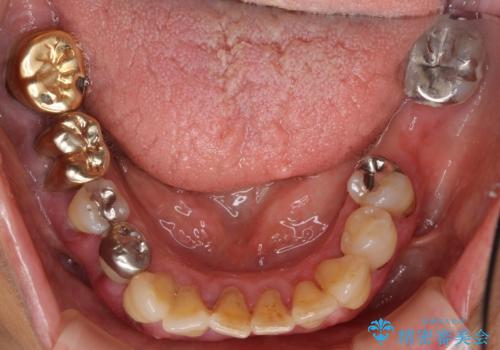

歯ぐきから血が出る、歯ぐきが腫れている 80代女性

- 歯ぐきからの出血と腫れを主訴に来院された患者様です。

プラークコントロールが非常に悪く、全顎的な歯周病に罹患していました。

「抜歯したくない、インプラントは嫌」という患者様のご希望とご年齢を考慮し、可及的な骨外科処置や根分割術によりできるだけ今ある歯を残す治療方針をたてました。

保存不可能な左上の奥歯2本(左上67)は抜去し、ノンクラスプデンチャーをいれることにしました。